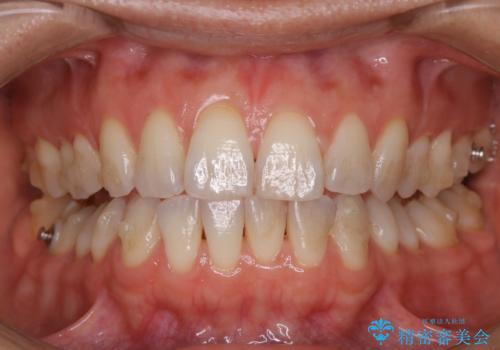

- インビザライン矯正治療中にステインが気になるとのことで来院されました。全体的にステインが付着していたため自費クリーニングPMTC(60分コース)を行いました。

インビザライン矯正治療中は、ご自身の歯にアタッチメントという突起物(効率的に歯の移動を行うため)をつけます。そのため、通常時よりもステインが付きやすい状態になることがあります。

インビザラインは透明なマウスピースなので、ご自身の歯にステインなどが付着していると、見た目に影響してしまうことがあります。